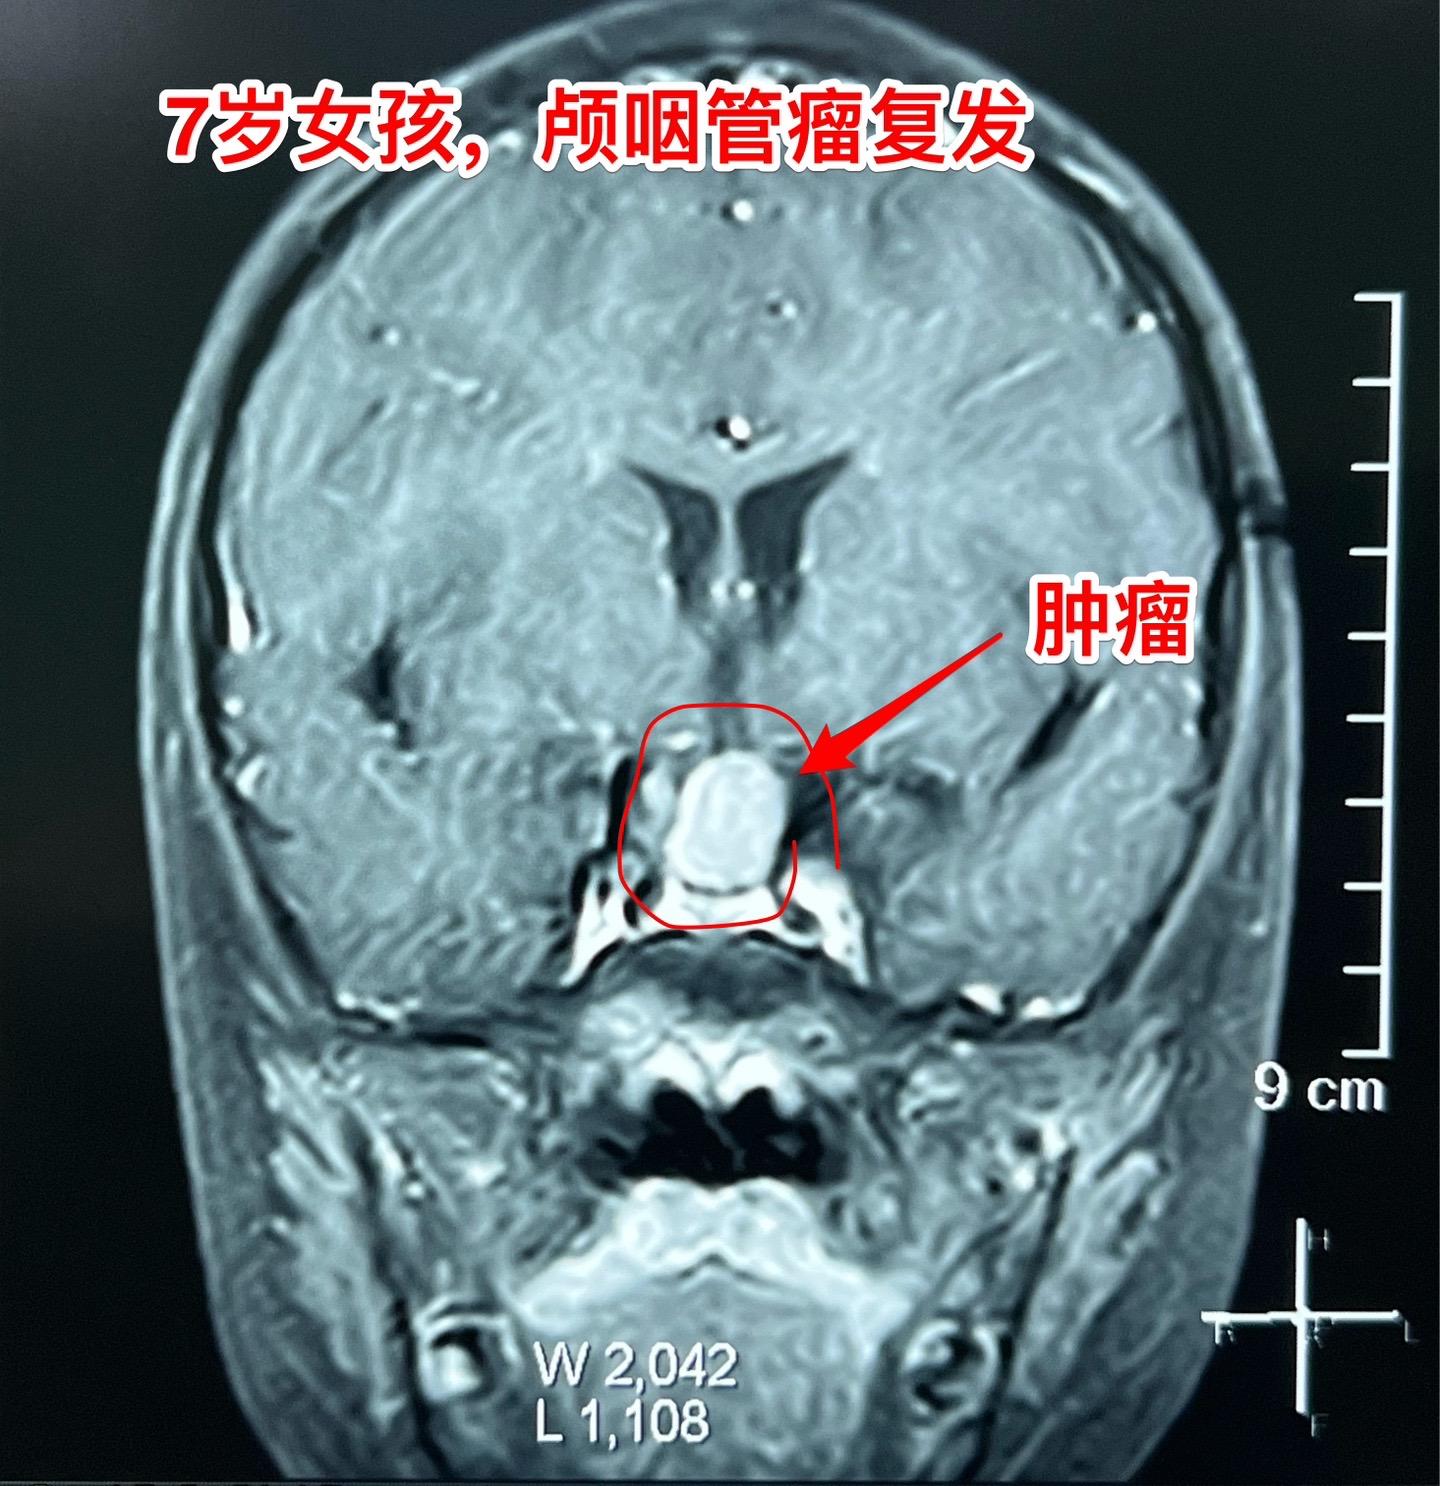

颅咽管瘤复发,看起来是一个瘤其实有三个。7岁女孩子,颅咽管瘤复发。从CT和磁共振来看,是一个大的囊性肿瘤,体积很大了,肿瘤向后颅窝生长,手术切除的难度还是比较大的。 2025年1月10日作手术过程中发现的情况比预想的还要复杂得多。除了这个大的囊性肿瘤之外还发现了两个孤立肿瘤。 这样的情况在我们科并不罕见,经常发现复发的颅咽管瘤病人脑部不止是一个瘤,有的时候有超过10个孤立的肿瘤。这种情况就要考验医生的技术和意志力了。当然,在我们科,总是争取把看见的瘤完全切除。